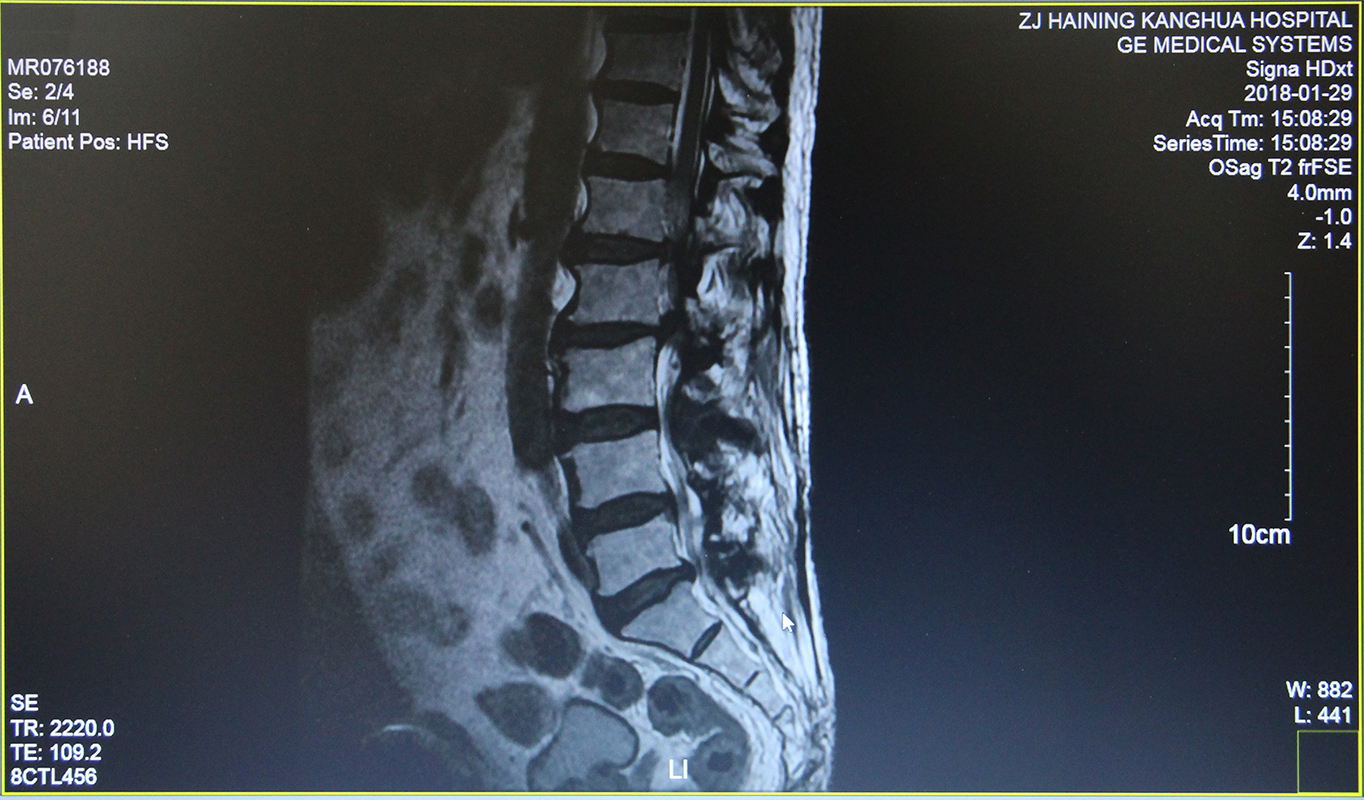

意识到事态不好,沈大伯来到海宁某医院就诊,腰椎MR检查显示——腰1/2、腰2/3椎间盘向左后侧脱出;腰3/4、腰4/5椎间盘向周边膨出;腰5/骶1椎间盘突出;腰椎重度椎管狭窄。医生建议住院治疗,沈大伯乖乖听从医嘱。然而治疗了约1周后,病情并没有得到改善。

(术前)